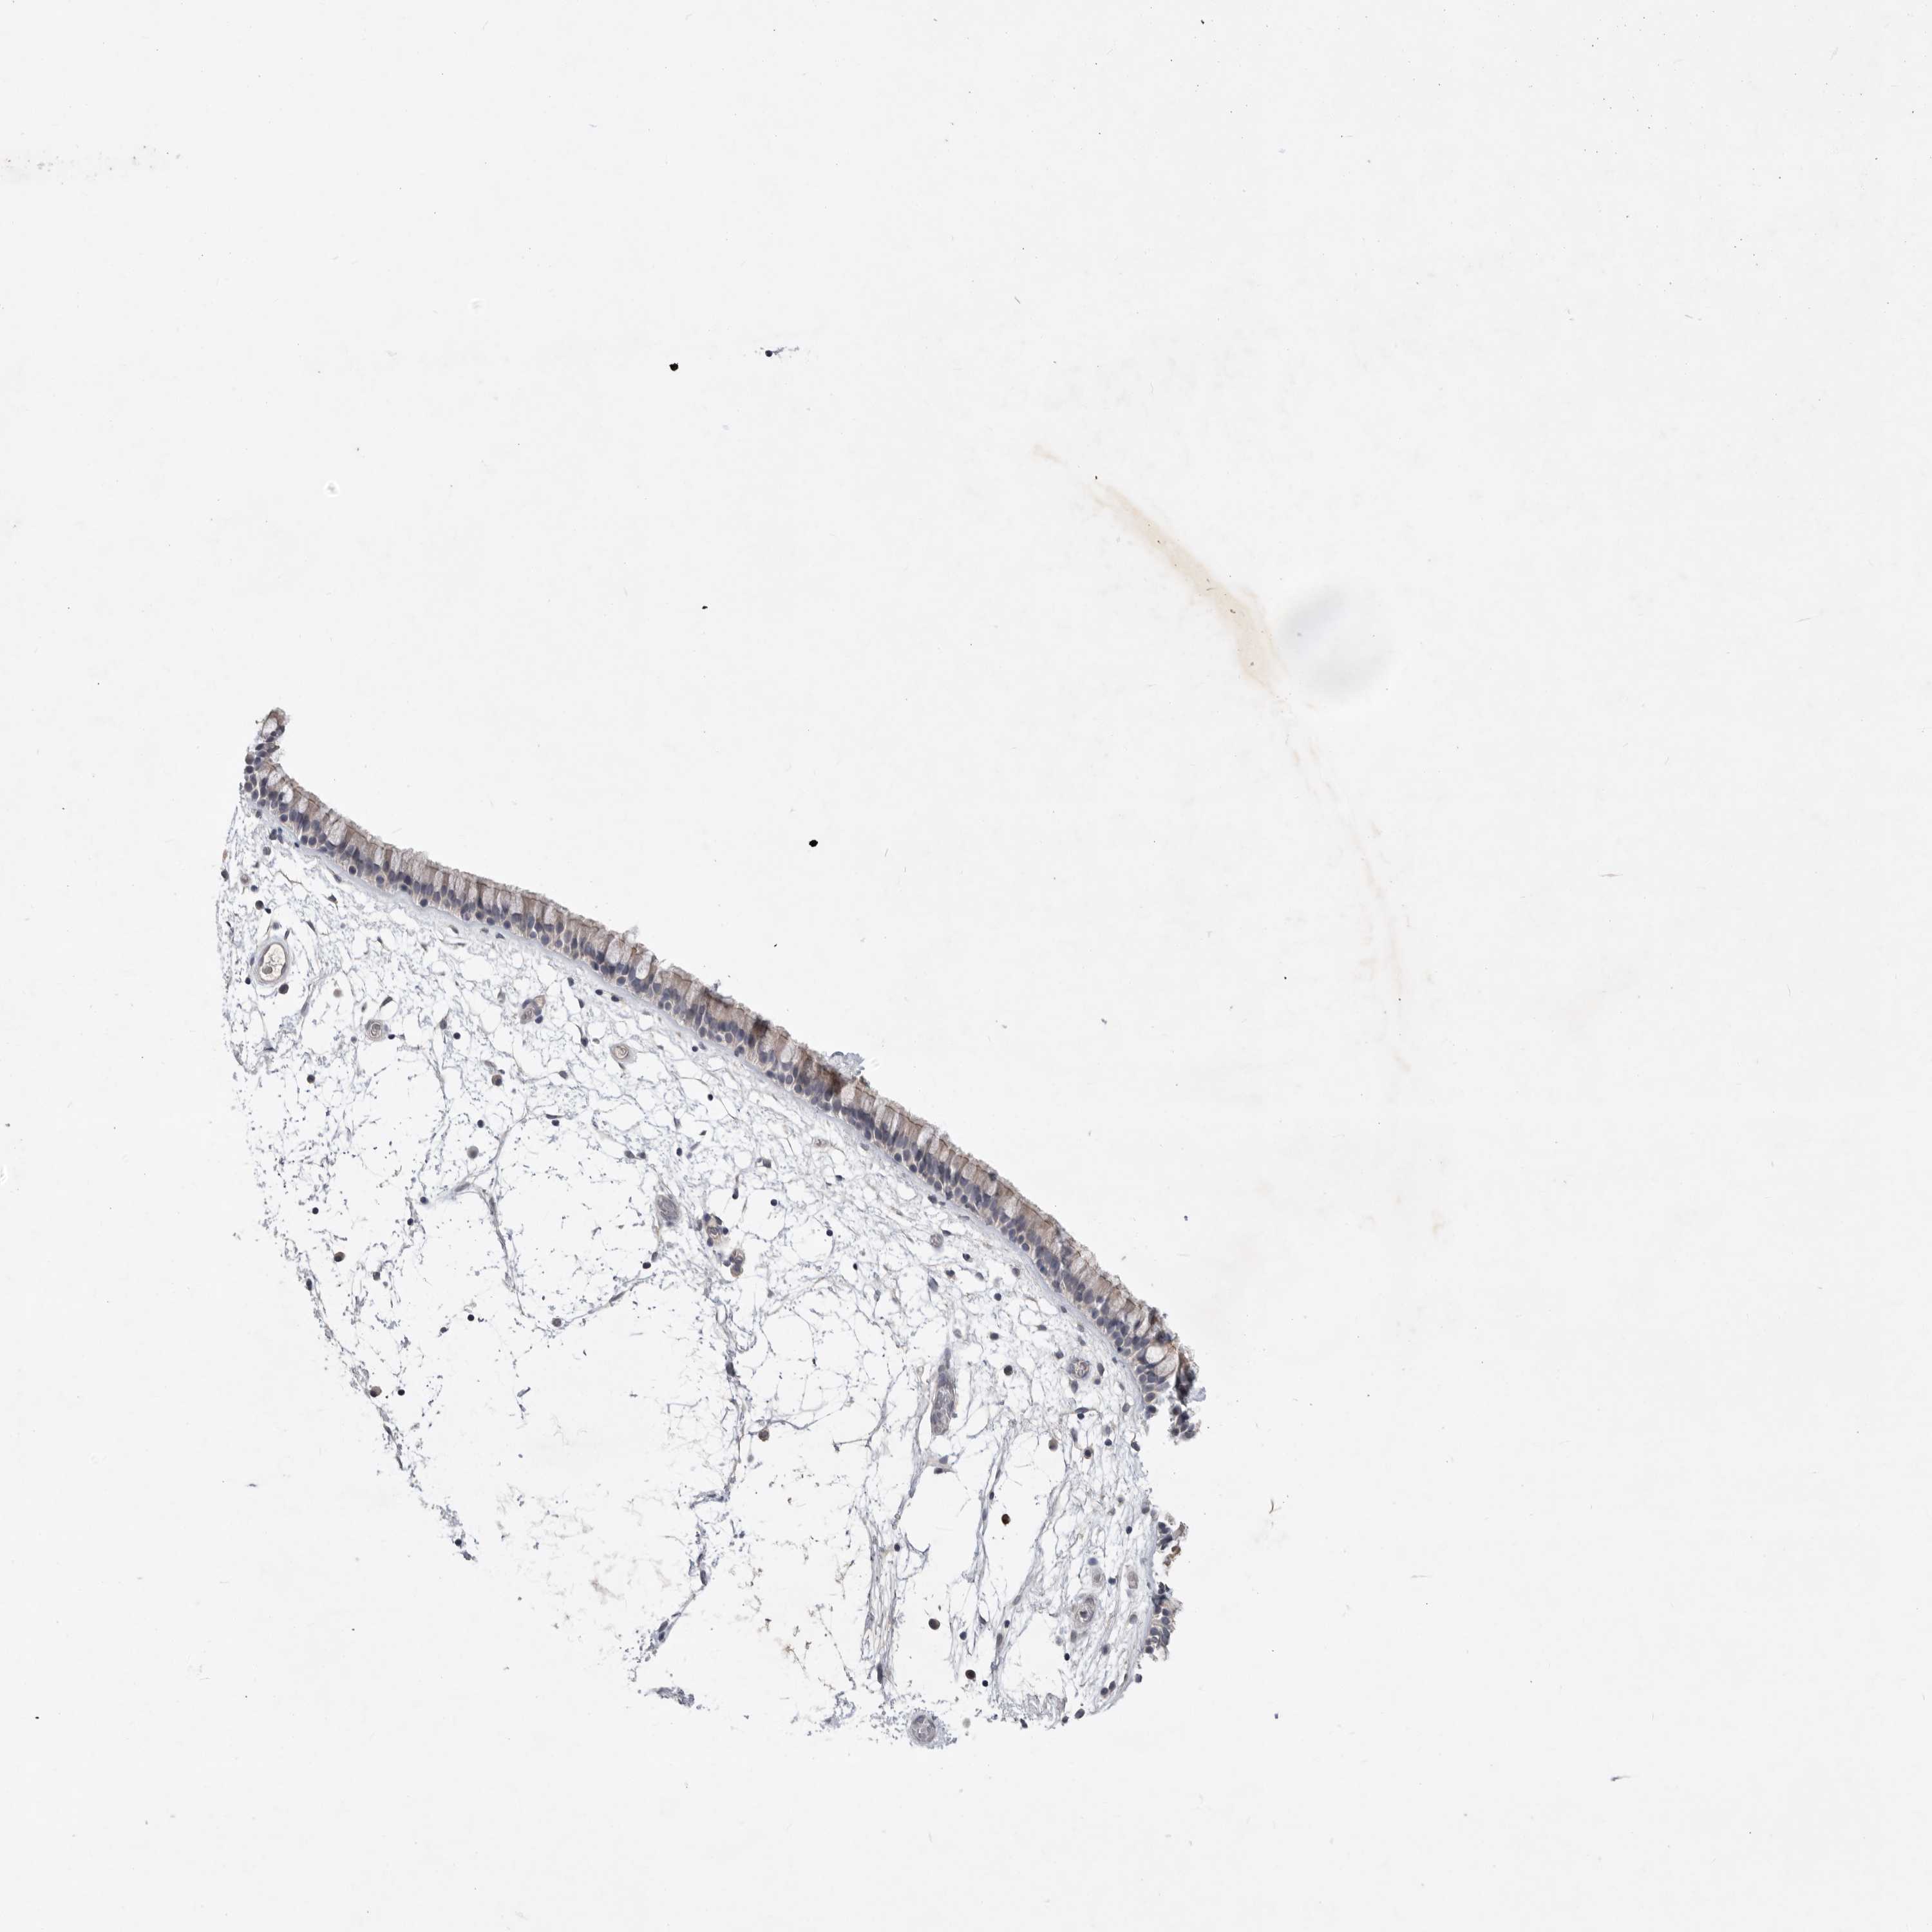

NASOPHARYNX - Antibody stainingi

Antibody staining in the annotated cell types in the current human tissue is reported as not detected, low, medium, or high, based on conventional immunohistochemistry profiling in selected tissues. This score is based on the combination of the staining intensity and fraction of stained cells.

Each image is clickable and will lead to virtual microscopy that enables deeper exploration of all samples and also displays staining intensity scores, fraction scores and subcellular localization as well as patient and tissue information for each sample.

Antibody HPA026786

Respiratory epithelial cells Not detected